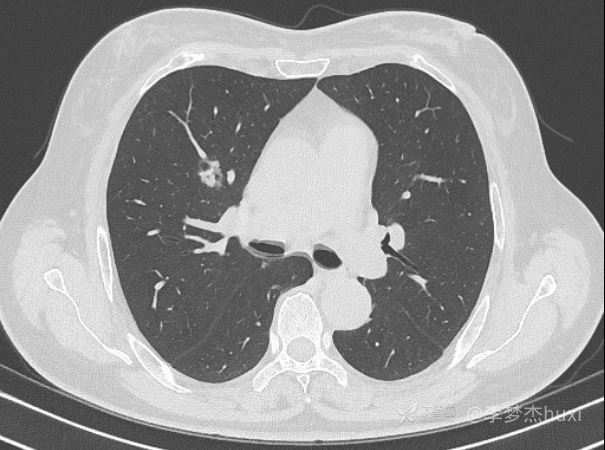

患者性别:女

患者年龄:61

主诉:体检发现肺结节

讨论:猜病理